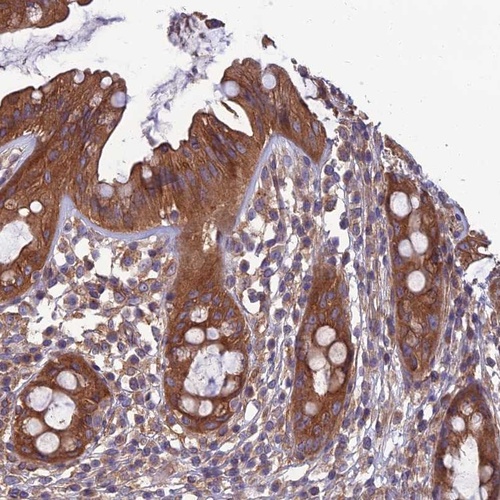

Immunohistochemical staining of human rectum shows strong cytoplasmic positivity in glandular cells.